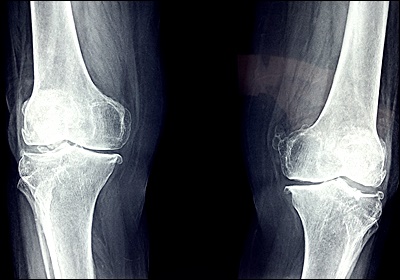

10. 경미한 관절 변형

류마티스 관절염이 진행됨에 따라 관절의 형태가 서서히 변할 수 있습니다. 초기에는 이러한 변화가 매우 미세하여 눈치채기 어려울 수 있지만, 시간이 지남에 따라 점차 뚜렷해집니다. 예를 들어, 손가락 관절이 약간 휘어지거나 튀어나온 것처럼 보일 수 있습니다. 또한 발가락이 옆으로 기울어지거나 발의 아치가 무너지는 현상이 나타날 수 있습니다. 이러한 변형은 관절 내부의 지속적인 염증으로 인해 연골과 뼈가 손상되면서 발생합니다. 초기의 경미한 관절 변형은 통증이나 기능 장애를 동반하지 않을 수 있지만, 시간이 지남에 따라 악화될 수 있으므로 조기에 발견하고 관리하는 것이 중요합니다.